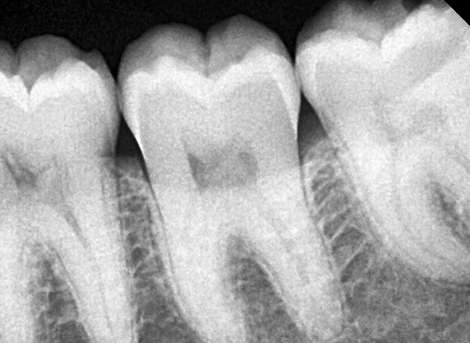

BEFORE & AFTER

Real Smiles. Real Stories.

From pain to perfect real patient stories